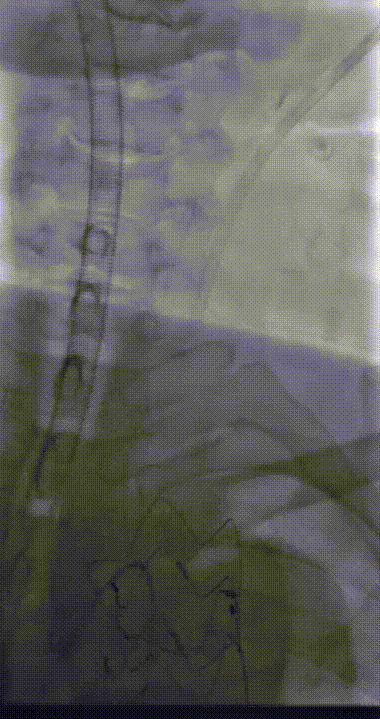

1. 入路操作

经左侧股动脉植入导管,造影显示胸主动脉无假腔,在内脏动脉区域存在较大破口。左侧颈动脉切开植入8F短鞘,造影证实颈动脉通畅。这一步骤为后续操作建立了重要通道,确保手术器械顺利进入体内。

2. 支架植入步骤

① 升主动脉模块植入

升主动脉模块型号:WFA-AS-46-46-12-12-60,直径46mm,两个内嵌分支12mm,长度6cm。

升主动脉模块输送器设计特点是Tip头短且预弯,使跨弓顺利。

定位主要依据远端。远端定位在无名动脉开口近心端。输送器缓慢释放,释放过程中需将血压控制在100mmHg左右。支架近端Tip头后释放回撤时要小心,避免剐蹭内嵌分支。